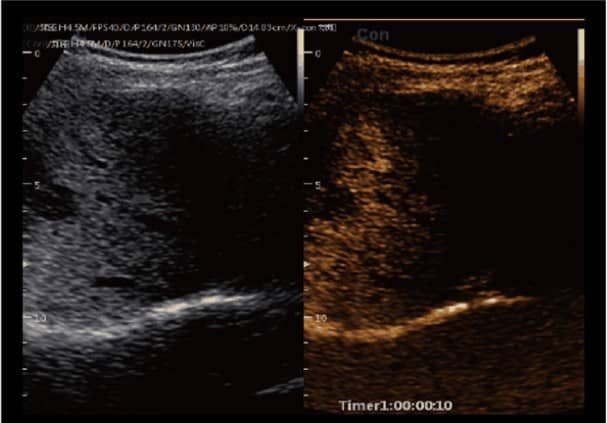

– Nó có khả năng chụp ảnh đa phương thức cùng với nhiều chức năng tự động như SonoColor , SonoCrystal , SonoAI-OB, Intelligent doppler, Sonocontrast , SonoNeedle , Color toàn cảnh , Dữ liệu thô …

- SonoColor và SonoContrast: Cung cấp phân tích dòng định lượng và độ nhạy cao hơn, thích ứng với mọi loại đầu dò.